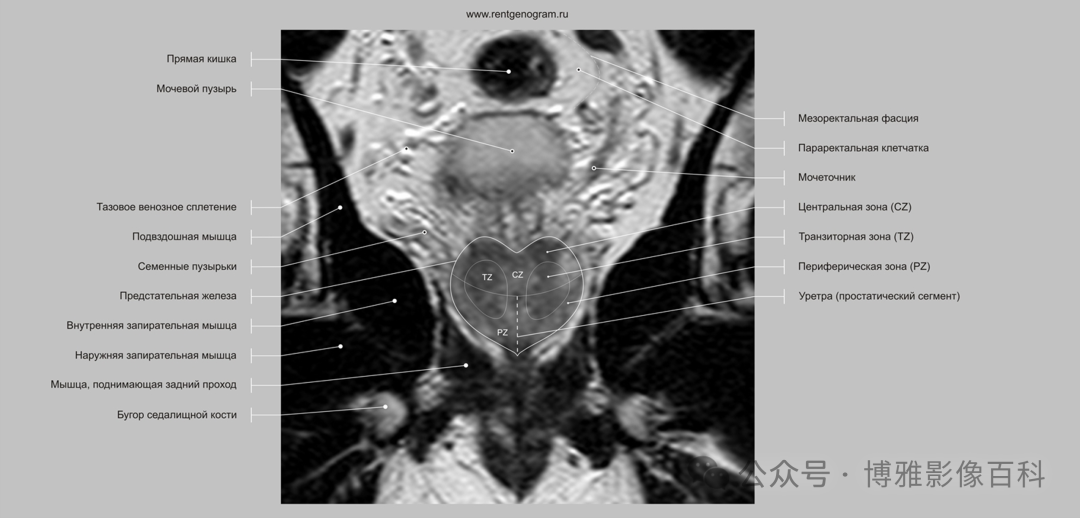

MR 解剖学

前列腺良性增生患者的轴向T2 图像,其他方面正常。外周带是一薄层均匀的高信号,边界清晰连续性的低信号包膜。移行带通常表现为不均匀中等信号,病灶被边界清楚的BPH良性前列腺增生结节所取代。精囊具有均匀T2高信号。未见淋巴结肿大。